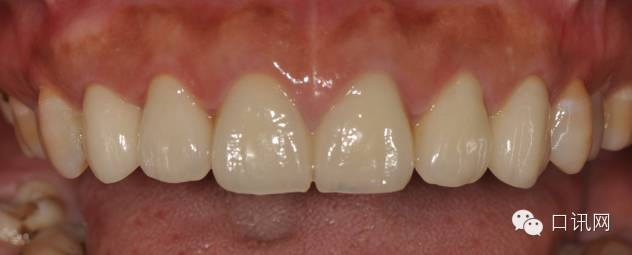

修复体完成后正面观

修复体完成口内照片